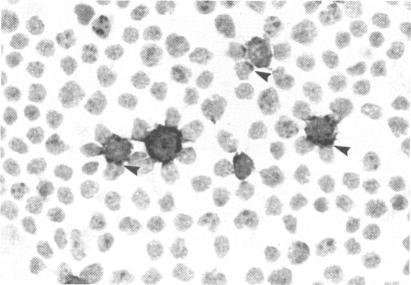

B cells, distinct from those seen in myasthenia gravis, are present in normal human thymic medulla, concentrated around the Hassall's corpuscles. We have shown that they constitute 33 +/- 4.8% of the total cells in the thymic medulla. In tissue sections they were often seen to have rosettes of thymocytes around them, a relationship which was maintained when the cells were isolated from the thymus. Thymic B cells expressed cytoplasmic immunoglobulins IgD, IgM and IgG but only rarely IgA. Unlike murine thymic B cells, human thymic B cells were CD5-. Freshly isolated thymic B cells were activated cells, but they rapidly became quiescent and died in culture over a 10-day period unless stimulated with mitogens. Thymic B cells responded to polyclonal B-cell activators SAC and TPA and when stimulated, maintained their relationship with thymocytes. Electron microscopic studies showed that two morphologically different thymocyte populations associated with the B cells. The plasma membranes of larger thymocytes were juxtaposed to the B-cell membrane, but smaller thymocytes with darker cytoplasm were associated with the B cells via cytoplasmic strands. Studies in mice have suggested that B cells are involved in thymic negative selection. The close association between activated B cells and thymocytes observed in this study supports this hypothesis.

与重症肌无力中所见的B细胞不同,正常人类胸腺髓质中存在B细胞,它们集中在哈氏小体周围。我们已经表明,它们占胸腺髓质总细胞数的33±4.8%。在组织切片中,经常可以看到它们周围有胸腺细胞形成的玫瑰花结,当从胸腺中分离出这些细胞时,这种关系依然存在。胸腺B细胞表达细胞质免疫球蛋白IgD、IgM和IgG,但很少表达IgA。与鼠胸腺B细胞不同,人类胸腺B细胞不表达CD5。新鲜分离的胸腺B细胞是活化细胞,但它们会迅速进入静止状态,并在培养10天内死亡,除非用丝裂原刺激。胸腺B细胞对多克隆B细胞激活剂SAC和TPA有反应,受到刺激时,它们会维持与胸腺细胞的关系。电子显微镜研究表明,有两种形态不同的胸腺细胞群体与B细胞相关。较大胸腺细胞的质膜与B细胞膜并列,但细胞质较暗的较小胸腺细胞通过细胞质细丝与B细胞相连。对小鼠的研究表明,B细胞参与胸腺阴性选择。本研究中观察到的活化B细胞与胸腺细胞之间的紧密联系支持了这一假设。